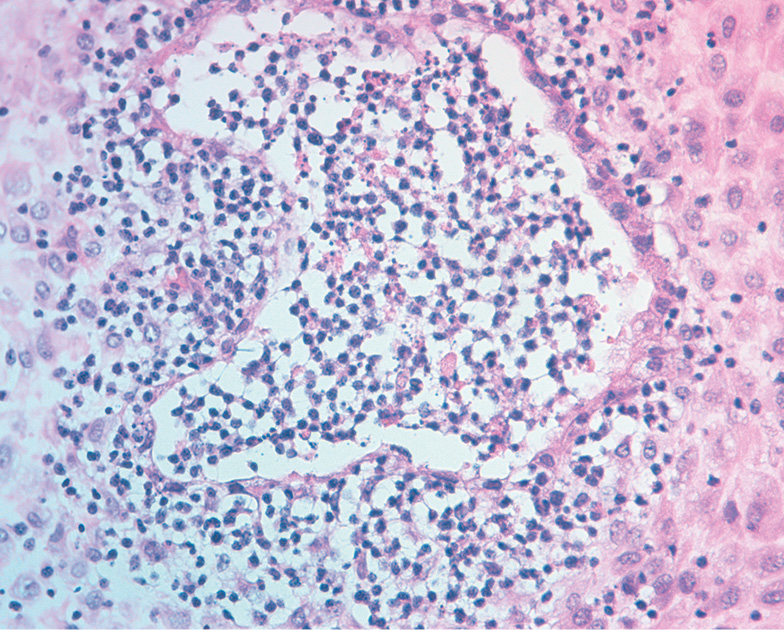

在形态上,两组绒毛绒毛膜都表现为低塑化,多为无血管绒毛。正常的核型显示绒毛基质轻度至中度水肿和轻微的硬化性改变(表1)。在染色体绒毛膜异常组中,观察到绒毛膜明显水肿和增厚的粗略结构变化(见表1)。此外,染色体异常组的滋养细胞坏死和间质间隙成簇的纤维蛋白样坏死场比整倍体组多2.4倍(p<0.05)(见表1,图1)。根据文献,这些变化可能是妊娠免疫排斥反应的间接征象[1]。

图1 染色体异常的绒毛:合并明显的增厚和水肿, 滋养细胞坏死,绒毛间的纤维素坏死区。苏木精-伊红染色,增大×100倍